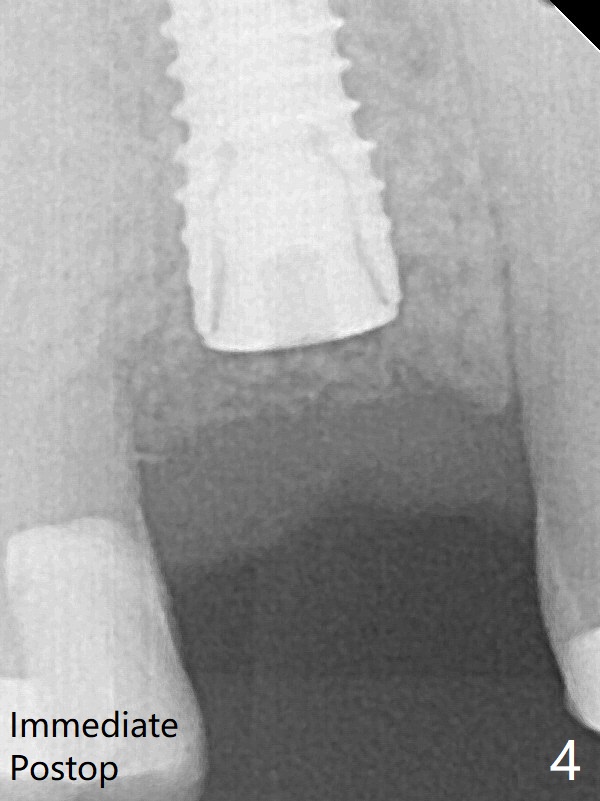

术后三个月根尖片显示骨粉减少(图八)。不可吸收膜脱落可能造成骨粉流失。应该做减张缝合。树脂敷料,而不是牙周敷料。其实缝合压扁骨粉,愈合或者细长的修复基台有支撑,减张作用。后面讨论。中央血供不够,伤口裂开。周围骨粉能成活就好。